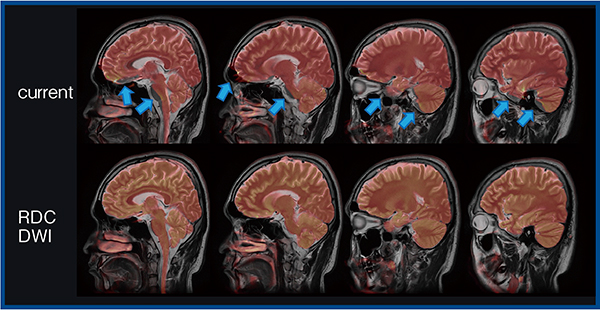

最後に,拡散強調画像(DWI)における歪み低減技術RDC DWIについて紹介する。RDC DWIは,位相エンコード方向が異なる2つの撮像を行い,各画像から歪み量を計算することで歪みを低減した画像を構築する技術である(図5)。RDC DWIはb0画像だけでなく,MPG印加画像においても位相エンコードの異なる撮像を行うことで,磁場不均一性に加え渦電流の影響による歪み補正も行え,より高精度の歪み補正が可能となる。実際の画像でも,RDC DWI適用により頭蓋底の歪みが低減したほか,RDC DWIとT2強調画像のフュージョン画像(図6,7)では,多断面にわたって歪み(↑)が大きく改善した。

眼窩部でのT2強調画像との構造学的類似度(SSIM)の測定を行った結果では,RDC DWIがconventional DWIと比較して有意にSSIMが高かった。また,脳幹前後径の計測では,T2強調画像との計測値差は,RDC DWIはconventional DWIより有意に小さかった。

臨床では視神経炎の評価におけるDWIの有用性が多く報告されており,RDC DWIでの撮像によりADC計測の正確性が向上すると考えられる。さらに,従来のDWIでは前頭蓋底の嗅球の評価は困難であったが,RDC DWIでは歪みなく明瞭に描出することが可能になり,今後の臨床における活用が期待される。

図6 RDC DWIとT2強調画像のフュージョン画像(アキシャル像)

図7 RDC DWIとT2強調画像のフュージョン画像(サジタル像)